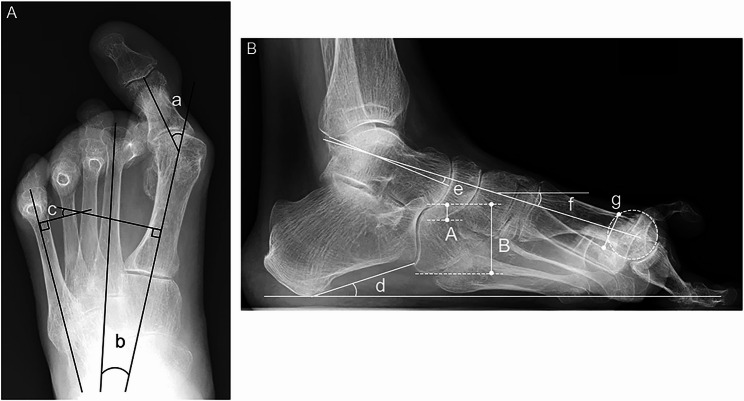

Impact of coronal and sagittal hindfoot alignment on metatarsus primus elevatus in patients with rheumatoid foot deformities.